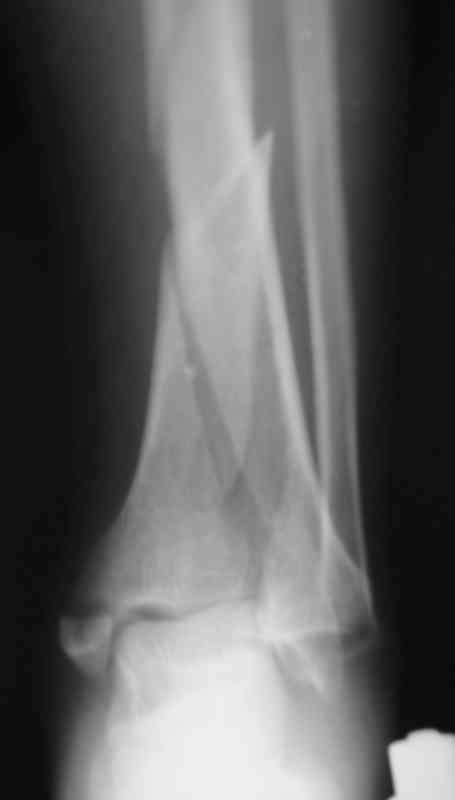

Сегодня прооперировали. Длительность 4-50. Начали как и говорил сверху вниз линейным разрезом - фиксация задне-латерального отломка к проксимальному 2мя винтами, затем "прилепили" к ним передне-медиальный (пришлось повозиться - была интерпозиция и довольно "сложный" винт) - к проксимальному 1 винтом и к задне-латеральному 1 винтом.Кстати на фото видно - у передне-медиального отломка еще осколок в области сустава, несколько смят. Далее началось веселье - второй доступ - задне-наружный к латеральной лодыжке и заднему краю, но оказалось, что задний край больше задне-медиальный (по снимкам было непонятно). Плюс к этому репозиция его мягко говоря сложновата (больной на спине, стол низкий и не поднимается). В общем выставили, фискировали 2мя винтами, на ЭОПе вроде стал, только верх отошел. Латеральную лодыжку заведующий решил интрамедуллярно (не хотел еще винты толкать), сначала 3мм спицей - нестабильно, затем 4мм стержень (не помню по автору) - ОК (кстати в месте перелома мелкая крошка - дефект до 5х7 мм по кортикалу). Ну медиальная лодыжка стандартно - третий разрез - винт 3,5 мм. Визуально все стабильно. На Р-контроле - видна небольшая ступенька заднего края по одному из контуров.

На фото простой суставной, метафиз. оскольчатый с переходом на диафиз перелом, пластина MIPO.

Фото с операции

Нельзя ли попросить снимки именно голеностопного сустава. Представлены снимки голени в нижней трети.Сустав фактичеси не виден.

Вы представили снимок голени в нижней трети. На сустав луч упал косо, это искажает.

Есть подозрение, что имеется ступенька заднего края, внутренняя лодыжка оттопырена. Взаимоотношения в суставе важнее, чем точная репзиция диафиза.

Коллеги подсказали различные варианты фиксации, включая минимальный открытый метод с фиксацией в аппарате Илизарова (Артемьев), а также перкутанный метод (Миронов) пластиной с угловой стабильностью.

Несмотря на различия методик, оба случаи, кстати сделанные на превосходном уровне, заслуживают внимания тем, что первостепенной задачей был поставлено восстановление суставной поверхности.

После восстановления сустава, не думаю, что были бы какие-то сложности в репозиции крупнооскольчатых переломов голени с применением минимально-открытой или закрытой методик.

Несмотря на анатомичность репозиции, полностью скелетированная нижняя треть!!! большеберцовой (на снимке) и стабильность фиксации вызывают беспокойство, обычно после такого склетирования удлиняются сроки сращения, и невозможно проследить на ренгенограмме признаков сращения в обычные сроки.

Методику минимальной фиксации никто не отрицает, но на диафизе она очень часто осложняется вторичными смещениями, и поэтому во всех случаях, даже при около- и внутрисуставных переломах, жесткость фиксации достигают установкой дополнительной нейтрализирующей пластины или наружными фиксаторами.